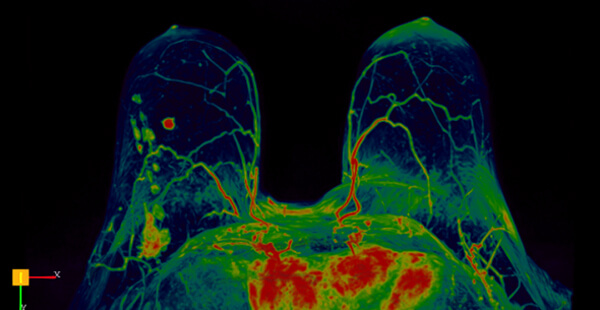

- Δυναμική αγγειογραφία (4D time resolved TWIST)

- Επεξεργασία των δεδομένων σε σύστημα CAD